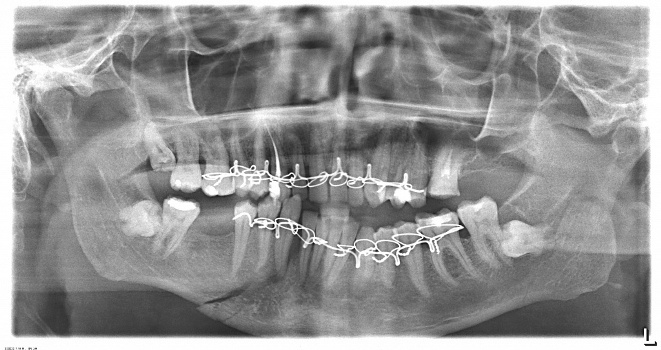

- ортопантомограмму (панорамный снимок зубов).

Это стоматологическое, рентгенографическое исследование, которое позволяет сделать панорамный снимок верхней и нижней челюсти, диагностировать большинство стоматологических заболеваний. С помощью аппарата для панорамного снимка используется ортопантомограф Sirona (Germany).

Ортопантомограмма - обзорный рентгеновский снимок челюстей, получаемый при помощи ортопантомографа.

Такие большие и детальные панорамные снимки позволяют врачу рассмотреть верхнюю и нижнюю челюсть, все зубы, их состояние, зачатки зубов, особенности пломб, высоту челюстей, их структуру, а также проследить за изменениями, возникшими в результате перелома нижней челюсти на всем ее протяжении.